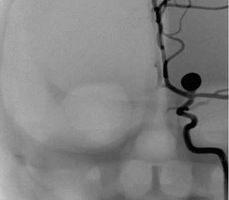

腎動脈介入手術(shù)模塊

可練習(xí)腎動脈支架手術(shù)的完整過程:造影診斷、導(dǎo)絲通過、導(dǎo)引導(dǎo)管的放置、保護(hù)傘的放置、預(yù)擴張、自擴張支架放置、后擴張、以及再造影等